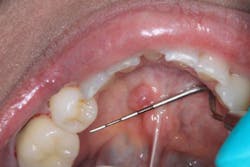

Figure 3: Radiograph from patient’s initial exam

A healthy 22-year-old female patient presented for a comprehensive examination (figure 3). She had no chief complaints and no caries. The patient was referred to an oral surgeon for removal of wisdom teeth. Following that, all contact was lost.